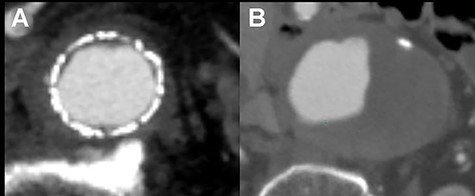

The patient recovered uneventfully, however, 1 year after open conversion, CT revealed a significant increase in the size of the unreplaced infrarenal aorta (Figs 3A, 4A and B). Reoperation was performed to treat the new aneurysm and on intraoperative findings, it was a true aneurysm. Abdominal aortic replacement was performed, however, infection of the vascular prosthesis occurred as a complication of this second open surgery. The infection was not controlled, and unfortunately, the patient died.

CT scan showing the significantly dilated infrarenal aorta, 1 year after open conversion (A, red arrow).